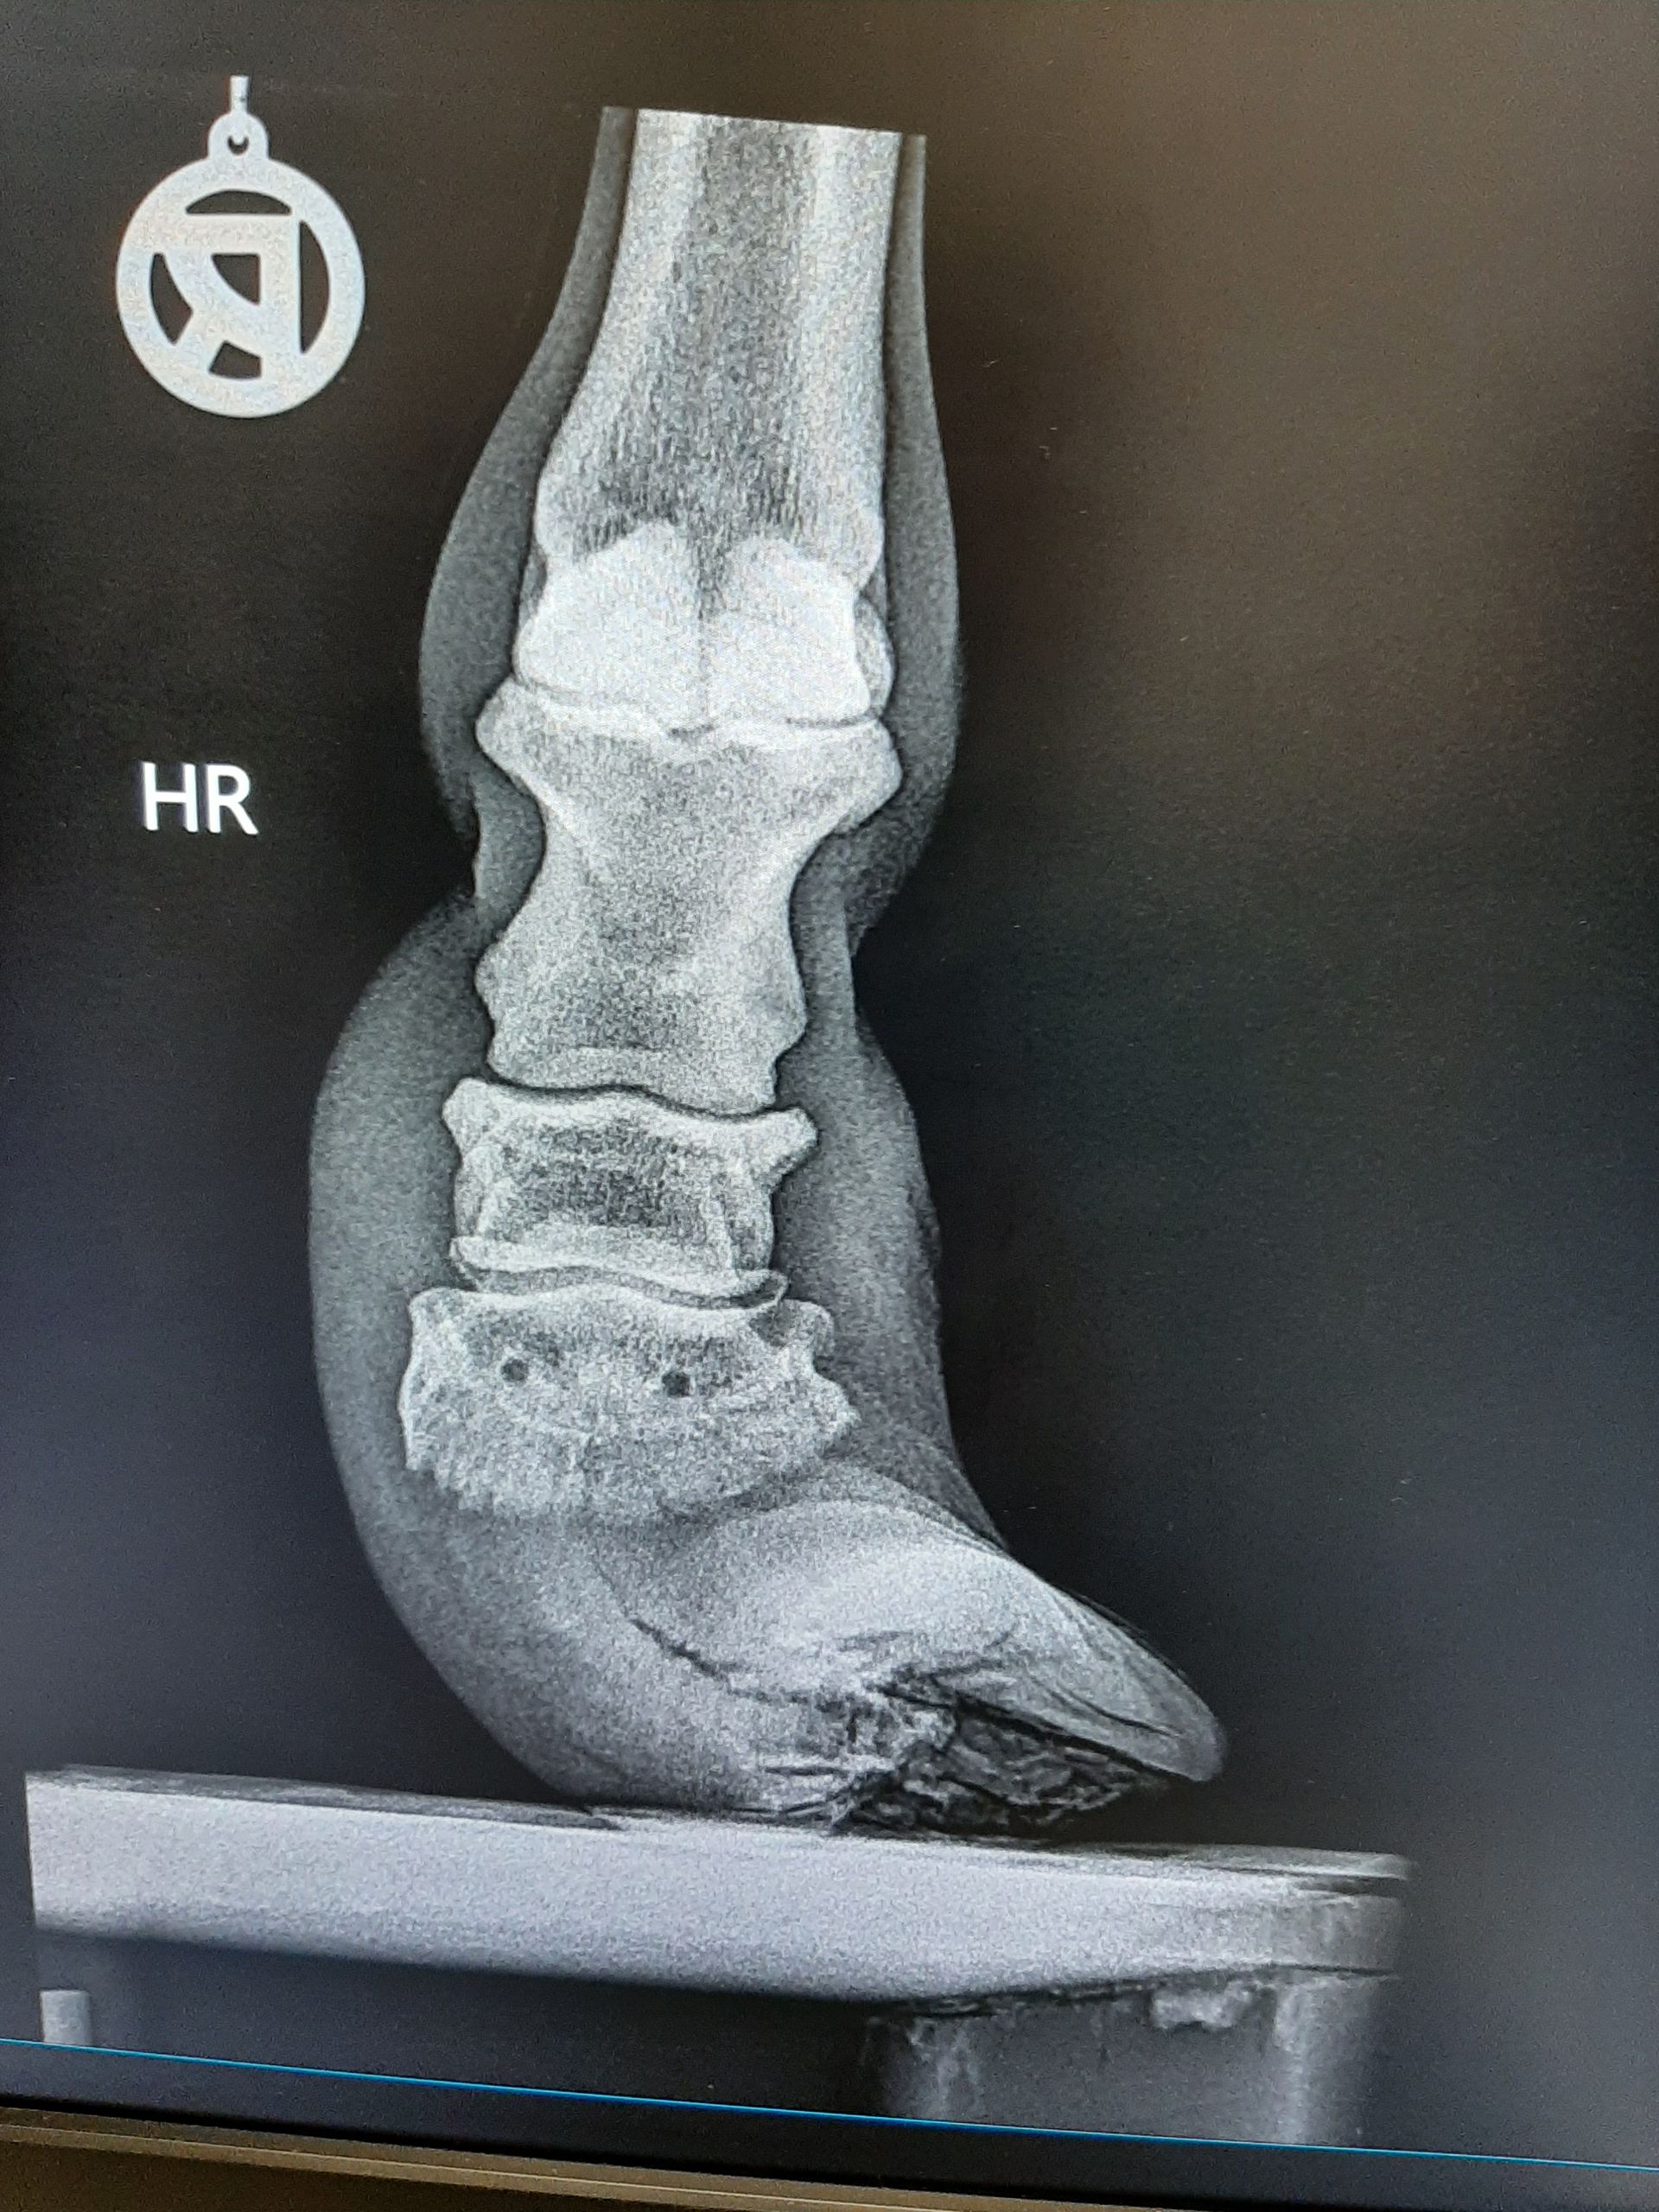

Fallbeispiel

Shetlandpony mit vernachlässigten Hufen

Behandlung: Entfernen des übermäßig gewachsenen Hufhorns

WaS war der Fall

Dieses Shetty wurde vorgestellt mit viel zu langen Hufen. Nach einer Kontrolle der Gelenken mittels Röntgenbildern wurde das überschüssige Horn entfernt.

Auf den Bildern sieht man, wie lang die Hufe sind. Nach dem Ausschneiden (Bilder fehlen leider) stand das Tier schon viel besser.